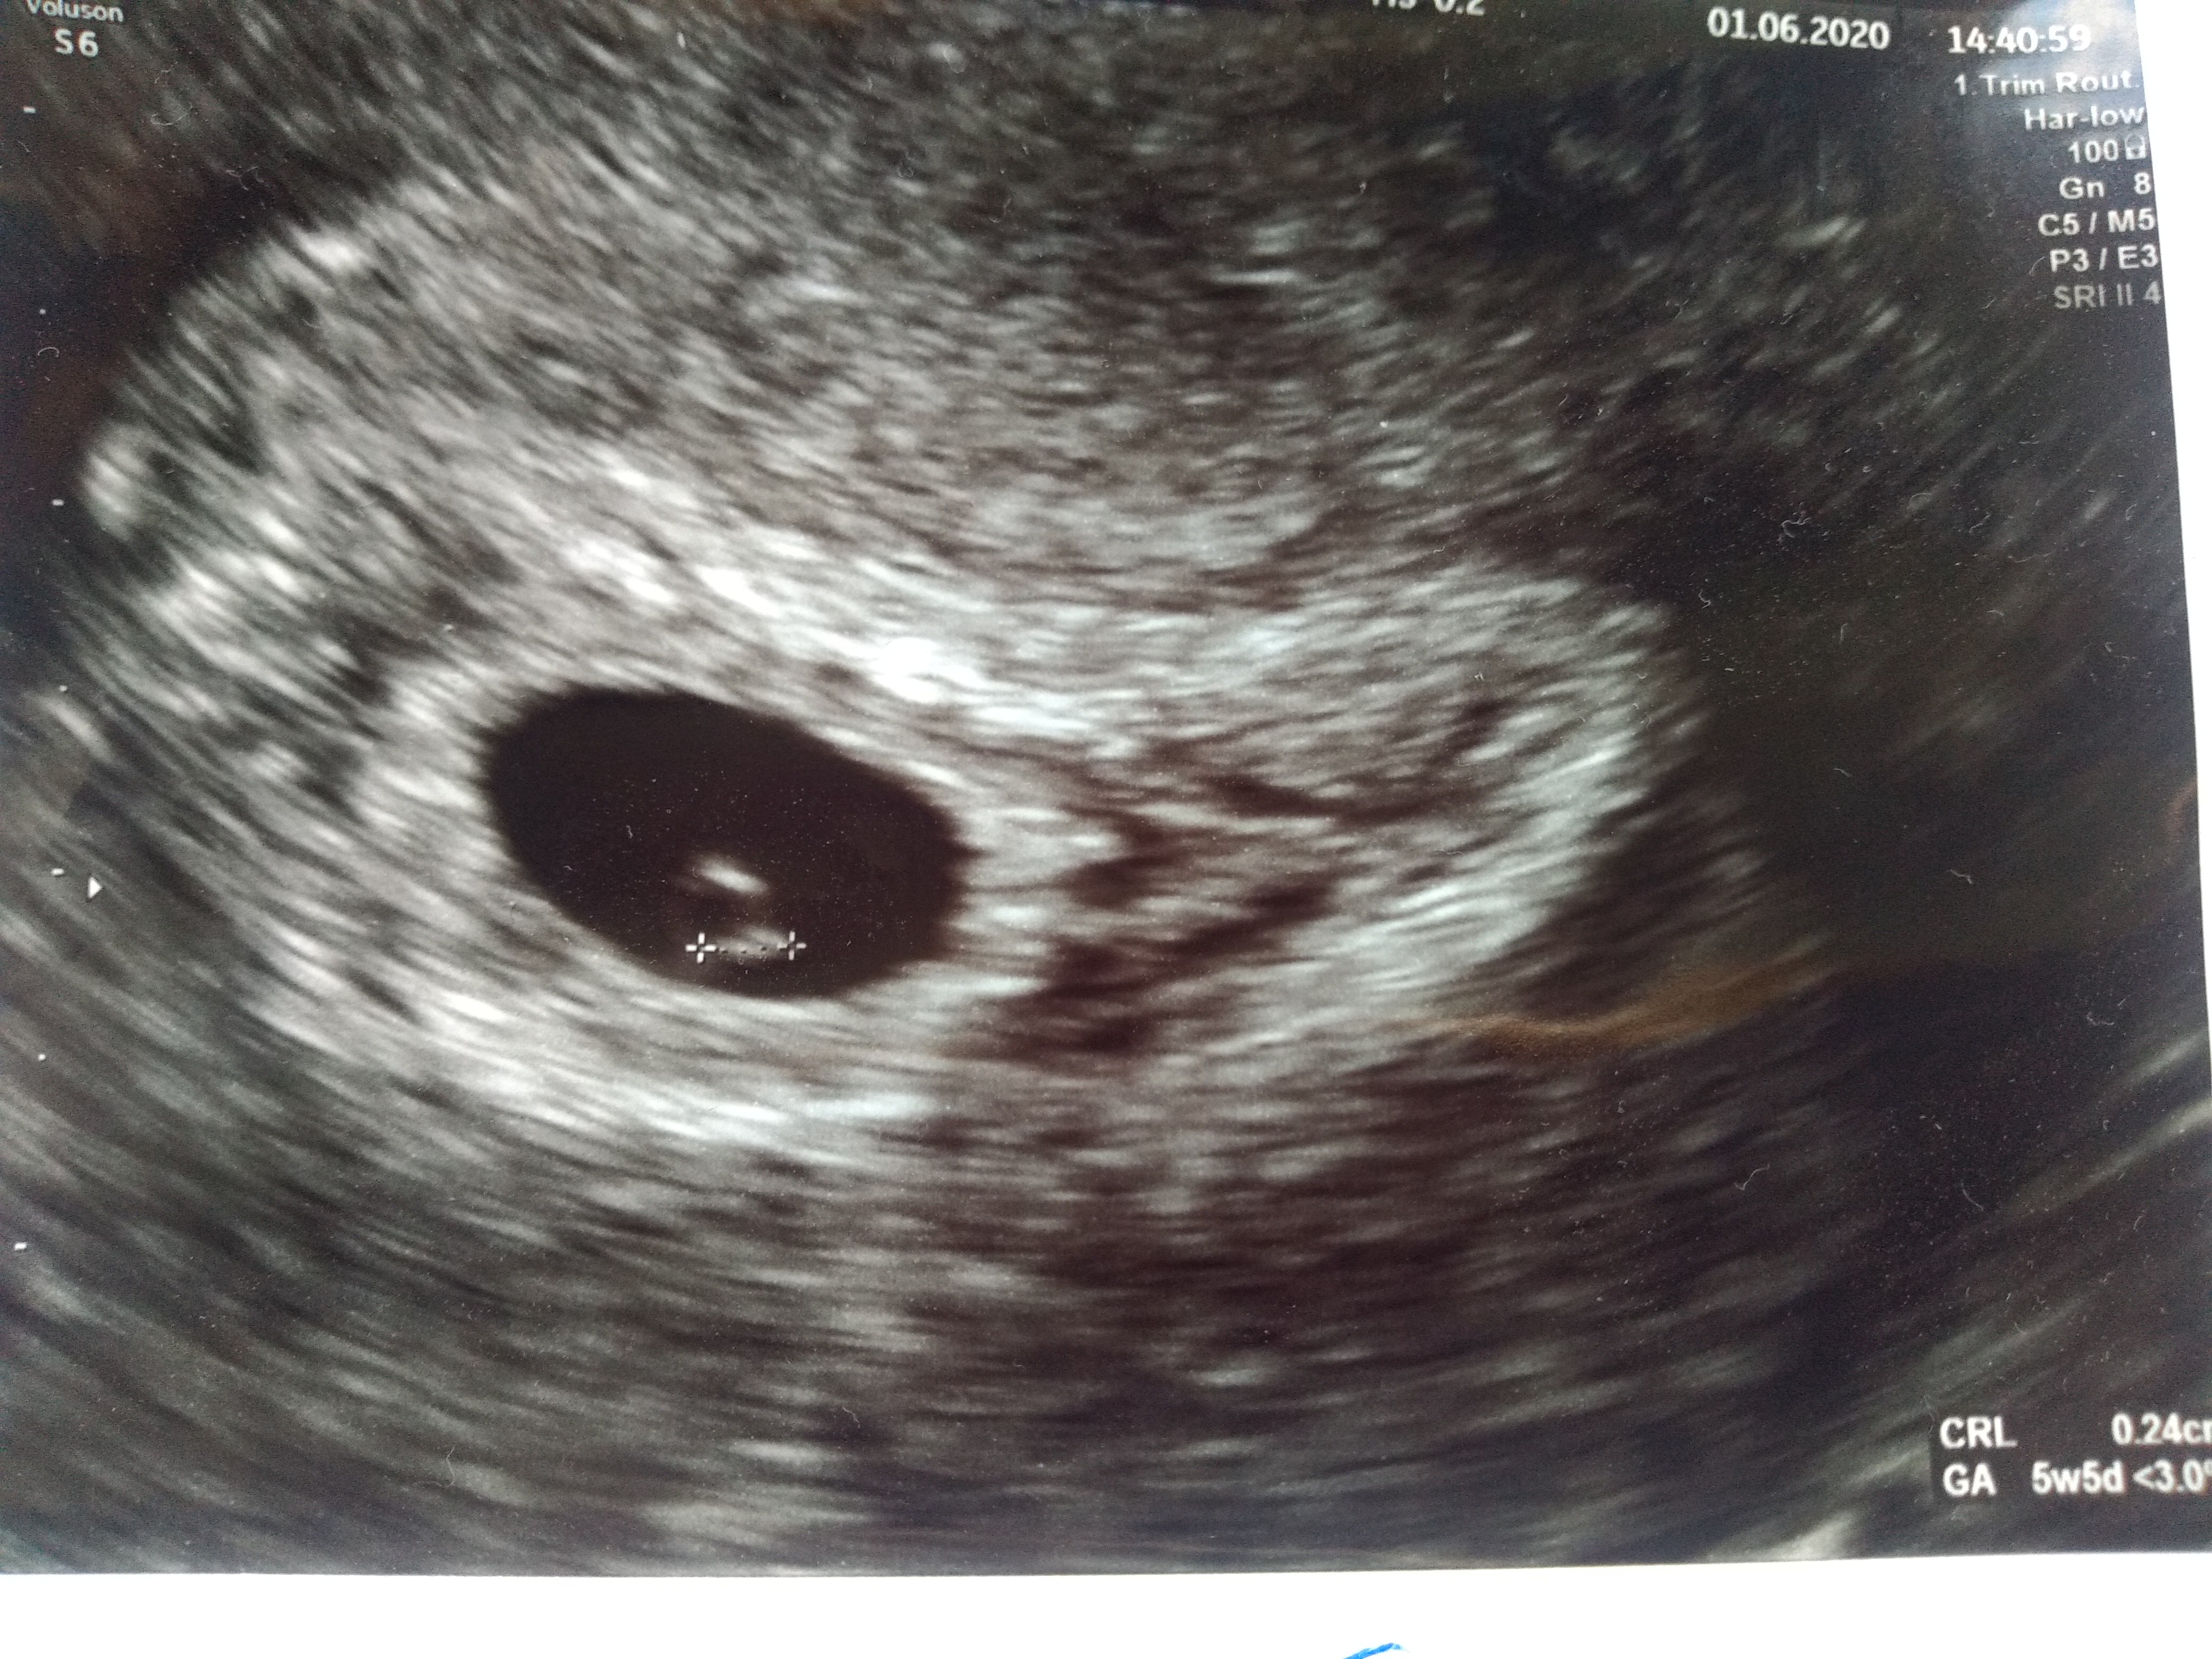

Po wczorajszej wizycie przespałam cały dzień.. Piękny kropeczek jest i serduszko też jest nawet je słyszałam przez chwilkę. Dostałam luteinę 2x dziennie bo "trochę słaba szyjka", chyba trochę zapobiegawczo bo 4 ciąża. Mam się oszczędzać itp. A tak poza tym to wszystko ok. Za 3 tygodnie kontrol. Termin z USG wyszedł dokladnie tak samo jak om.